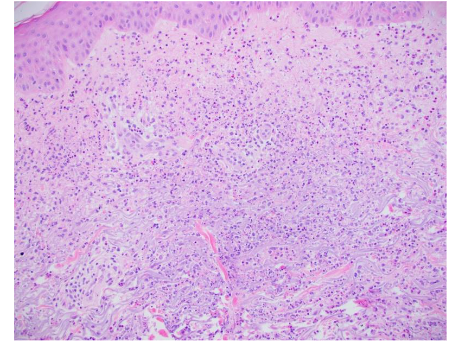

Pyoderma gangrenosum (PG) is the second most common cutaneous EIM associated with IBD, however, it is only present in 0.4-2% of patients, 1-2% of patients have UC. It is seen more commonly in CD, females, blacks of African descent and those with a family history of UC. In < 15% of patients, it occurs before the diagnosis of IBD, in some cases it parallels disease activity and in other cases, it follows an independent course. PG is a type of non-infectious neutrophilic dermatosis, similar to Sweet’s syndrome, that is associated with IBD in up to 30% of cases. Clinical presentation includes single or multiple painful erythematous lesions which can quickly develop into a blistered/necrotic ulcer with a violaceous and undermined border, most often manifesting on the legs or peristomal location. It may be accompanied by myalgia, arthralgia, fever and malaise. There are several variants of PG with the subtypes most associated with IBD being ulcerative, bullous, pustular and peristomal. It has been classified as a form of pathergy, which implies a significant skin injury after only a minor trauma. Microscopic findings for PG will differ depending on the variant but classically shows ulceration of the epidermis and dermis, along with a marked neutrophilic infiltrate undermining the epidermis, neutrophilic pustules and abscess formation. In general, PG is a very difficult diagnosis to make and is considered a diagnosis of exclusion after bacterial, fungal and mycobacterial causes of ulceration have been ruled out. Due to this, it is paramount when performing a biopsy for evaluation that the active border of the ulcer be included and that the sample penetrate into the subcutaneous tissues.